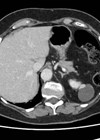

Case 1 A 67-year-old gentleman underwent a CT scan after presenting with visible haematuria and weight loss. His comorbidities include hypertension, type II diabetes mellitis and hypercholesterolaemia. He is a smoker. Figure 1. Figure 2. What do Figures 1 and...